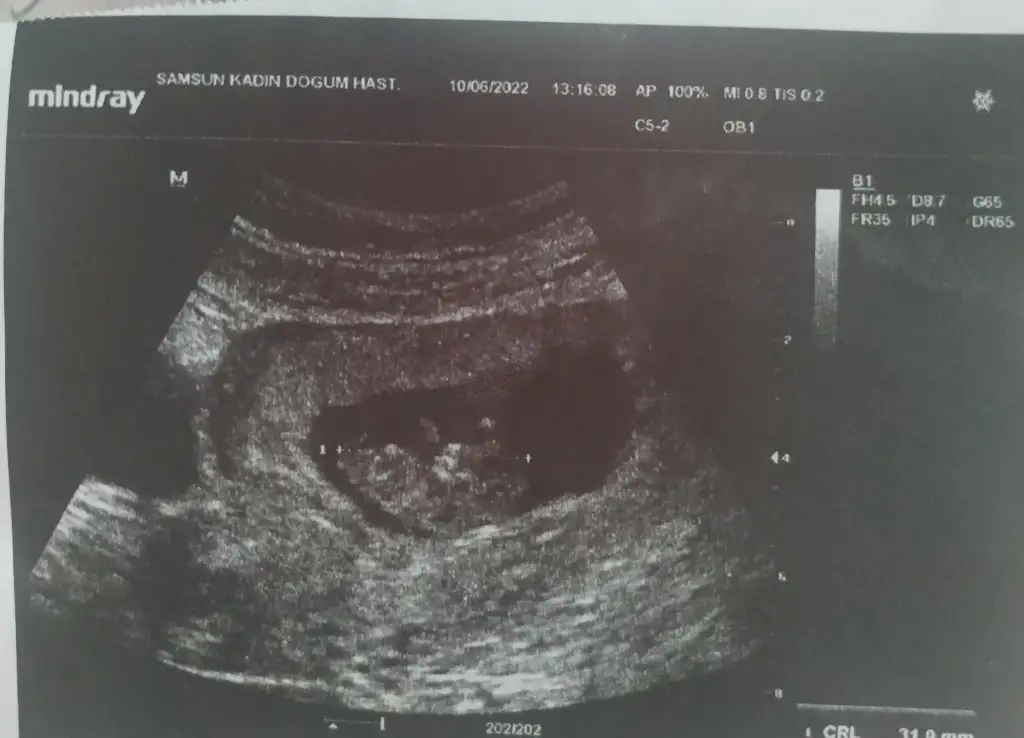

5 ve 14. haftaya kadar olan ultrason fotolarınızı paylaşın. Vajinadan mı yoksa karından mı çekildiğini ve kaç haftalık olduğunu da mutlaka belirtin.:anneadayı:

8+1 vajinal ultrason yorum yaparsanız sevinirim teşekkür ederim

Merhaba 13+3 karından çekılmıs ultrason. Tahmınınız nedir rica etsem?